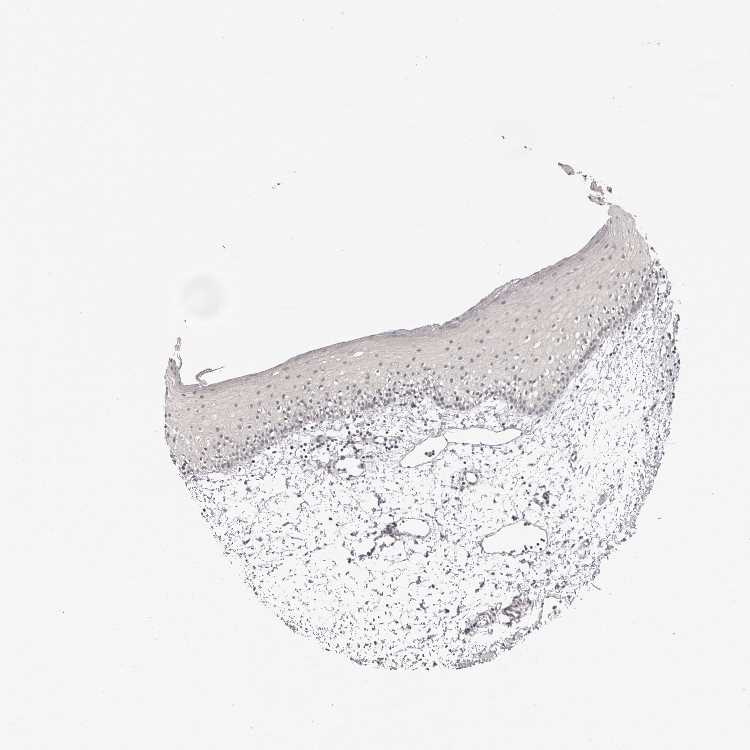

ORAL MUCOSA - Antibody stainingi

Antibody staining in the annotated cell types in the current human tissue is reported as not detected, low, medium, or high, based on conventional immunohistochemistry profiling in selected tissues. This score is based on the combination of the staining intensity and fraction of stained cells.

Each image is clickable and will lead to virtual microscopy that enables deeper exploration of all samples and also displays staining intensity scores, fraction scores and subcellular localization as well as patient and tissue information for each sample.

Antibody HPA030637

Squamous epithelial cells Not detected